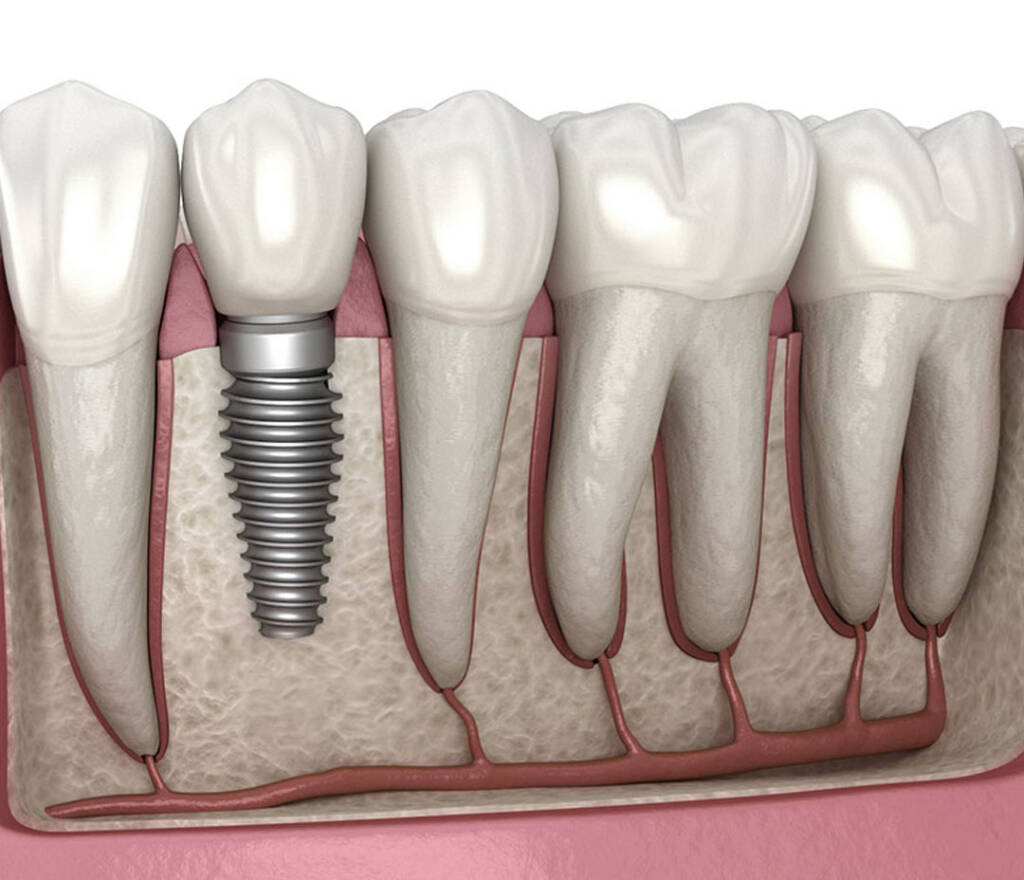

A dental implant is a biocompatible device placed into the jawbone to support a prosthetic tooth or restoration. Unlike removable dentures or bridges, implants are designed to integrate directly with bone tissue, providing stable and long-lasting tooth replacement.

A core principle of implant dentistry is osteointegration—the chemical and mechanical bonding between bone and implant surface.

Important features:

- Peri-implant bone is rich in blood vessels

- Newly formed cells populate tubule-like spaces between bone fibers

- Controlled bone remodeling stabilizes the implant over time

Implant stability is achieved through:

- Calcium-based chemical bonding between implant surface and bone minerals

- Mechanical interlocking within mineralized bone tissue

This dual bonding mechanism allows implants to mimic the anchorage of natural teeth—without relying on a periodontal ligament.

Unlike natural teeth, implants lack a periodontal ligament, meaning their success relies entirely on direct bone contact and tissue health.